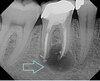

* Periodontitis periapicalis chronica cum fistula * (Chronic apical periodontitis with fistula) → Gutta-percha point tracing to apex

Apical radiolucency with sinus tract marker leading to apex – diagnosis?

• Periodontitis periapicalis chronica cum fistula

• (chronic apical periodontitis with fistula).

• Treatment: RCT or extraction